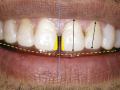

Bezpośrednia licówka kompozytowa w odcinku przednim wykonana…